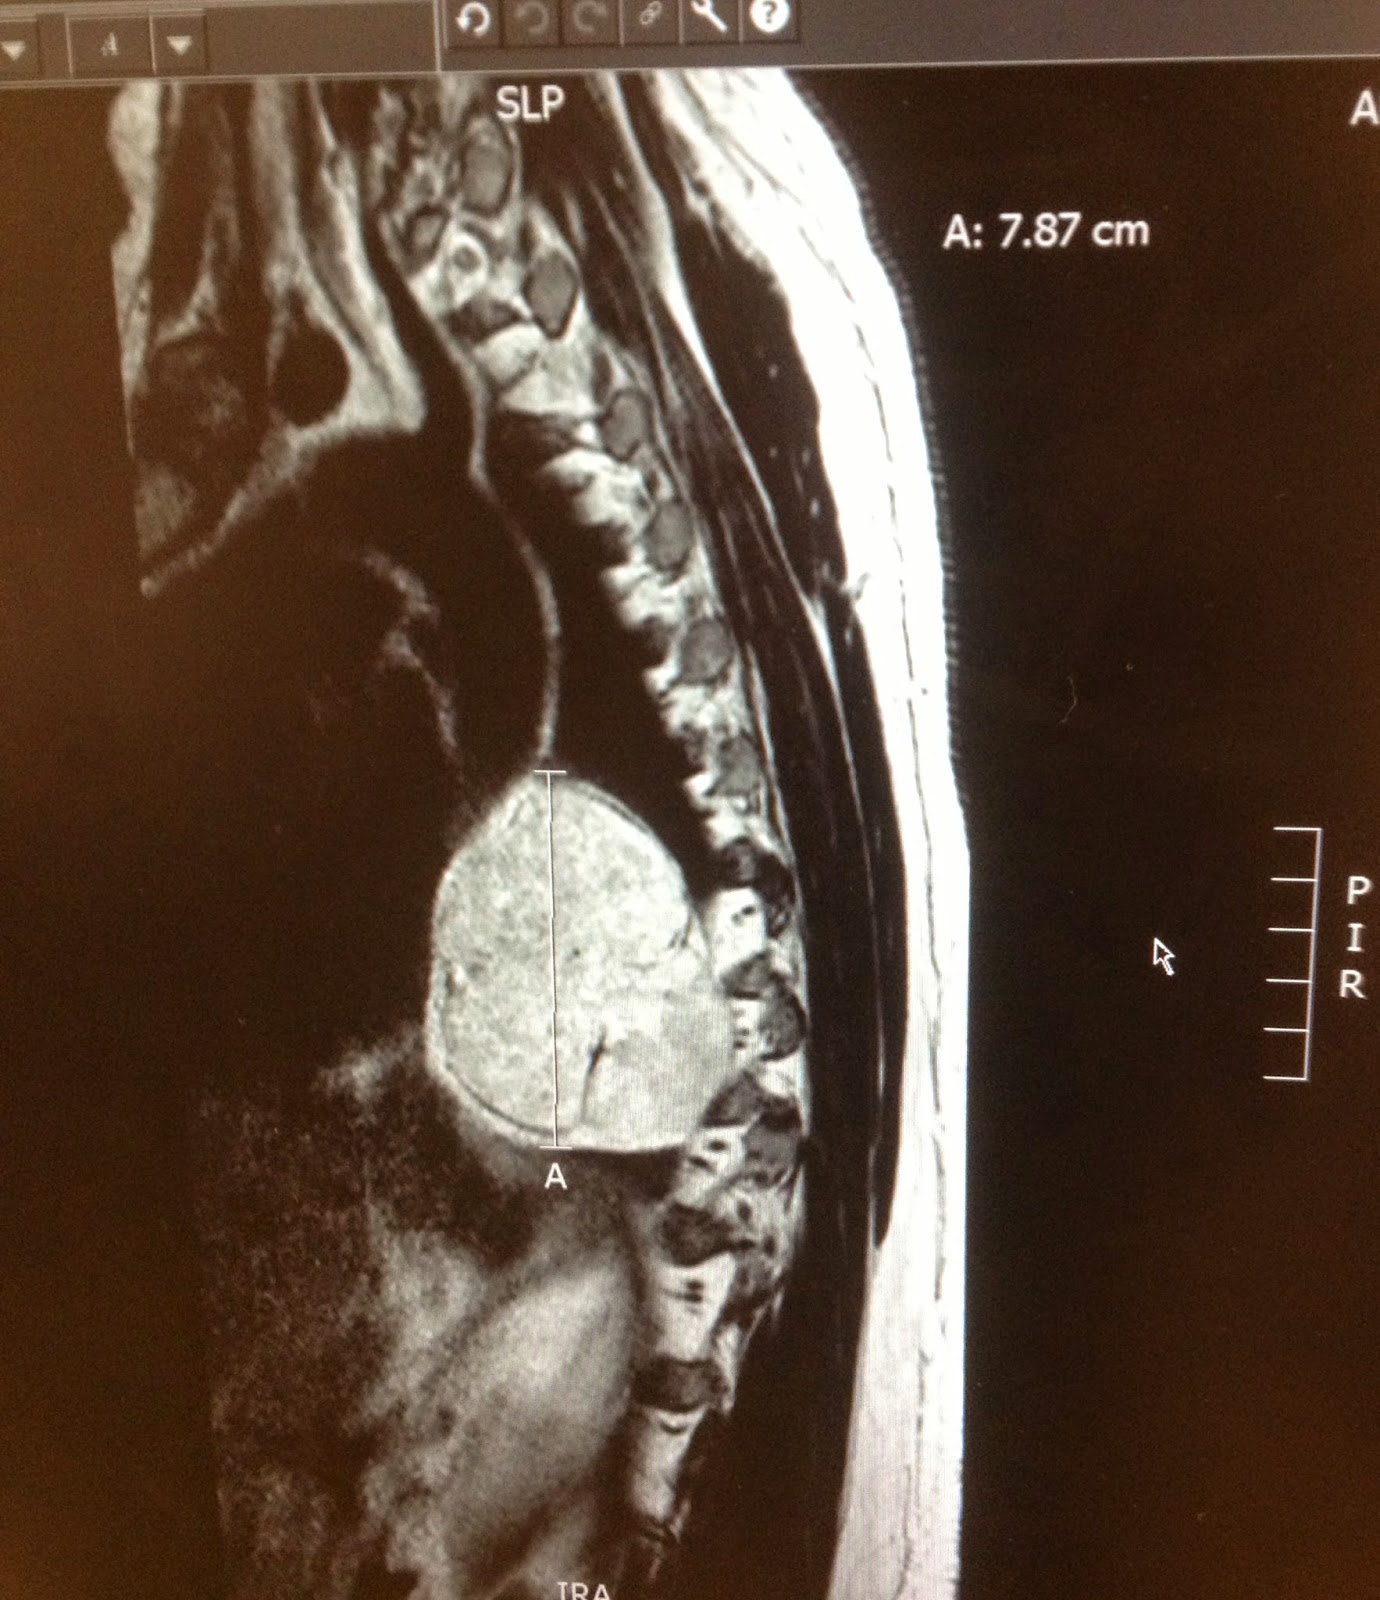

| We hadn’t seen this MRI view before. Greg saw Dr. Hayden recently and we asked if we could see an image of his sisters’ tumors. The large white thing attached to her spine is the chordoma. Ugh |

Today my post centers around Jackie – anything abnormal there?? How about that chordoma?? – the rare cancer that occurs in middle-age men with tumors at either end of the spine – Jackie is a teenage girl and for her it grows right in the center of her body. Abnormal can also be good – it was operable, she did not lose any vital functioning, and there is (so far) no radiation treatment.